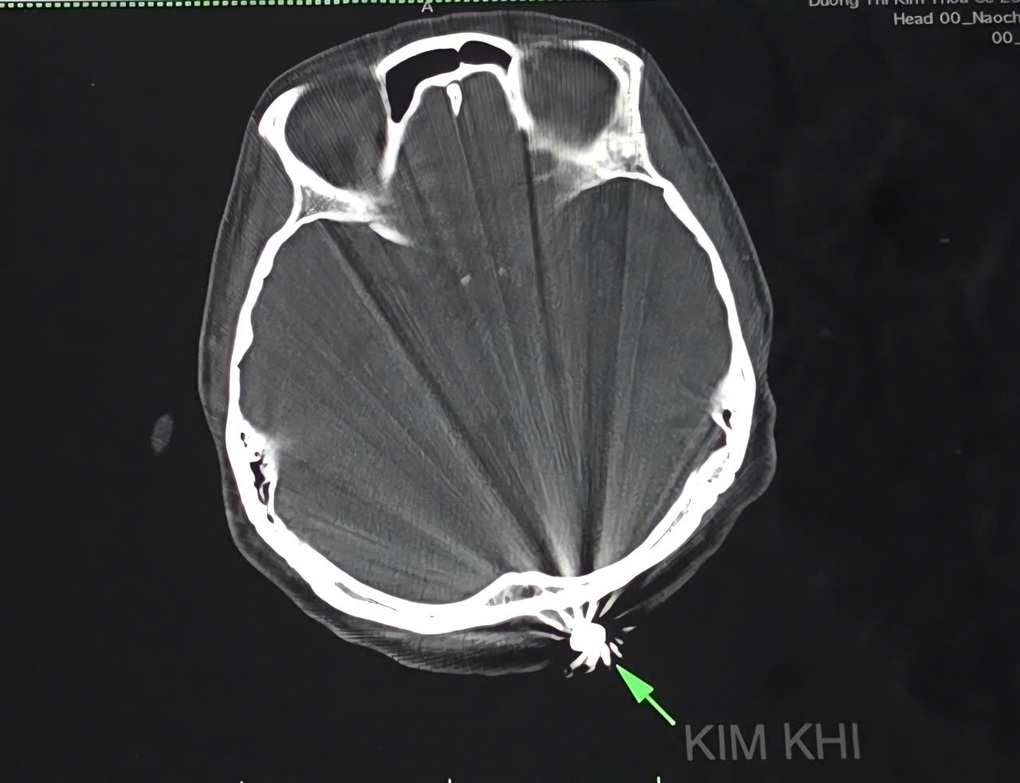

Hình kim khí trên phim chụp cắt lớp vi tính (Ảnh: Bệnh viện cung cấp).

Bà T. được người nhà đưa đến Bệnh viện Đa khoa Trung ương Cần Thơ lúc 18h41 cùng ngày trong tình trạng đau đầu, vết thương vùng chẩm khoảng 1cm đã cầm máu. Bên cạnh vết thương có một khối cứng hình tròn, kích thước 0,5x0,5cm.

Sau khi hội chẩn, các bác sĩ Khoa ngoại thần kinh quyết định phẫu thuật lấy dị vật và xử trí tổn thương; mở rộng vết mổ khoảng 3cm lấy ra dị vật kim khí là đầu đạn.

Ca phẫu thuật diễn ra thuận lợi, mất khoảng 45 phút thực hiện xong. May mắn viên đạn chỉ xuyên qua lớp da, chạm nhẹ vào xương chẩm, không gây tổn thương đến não và cấu trúc lân cận.